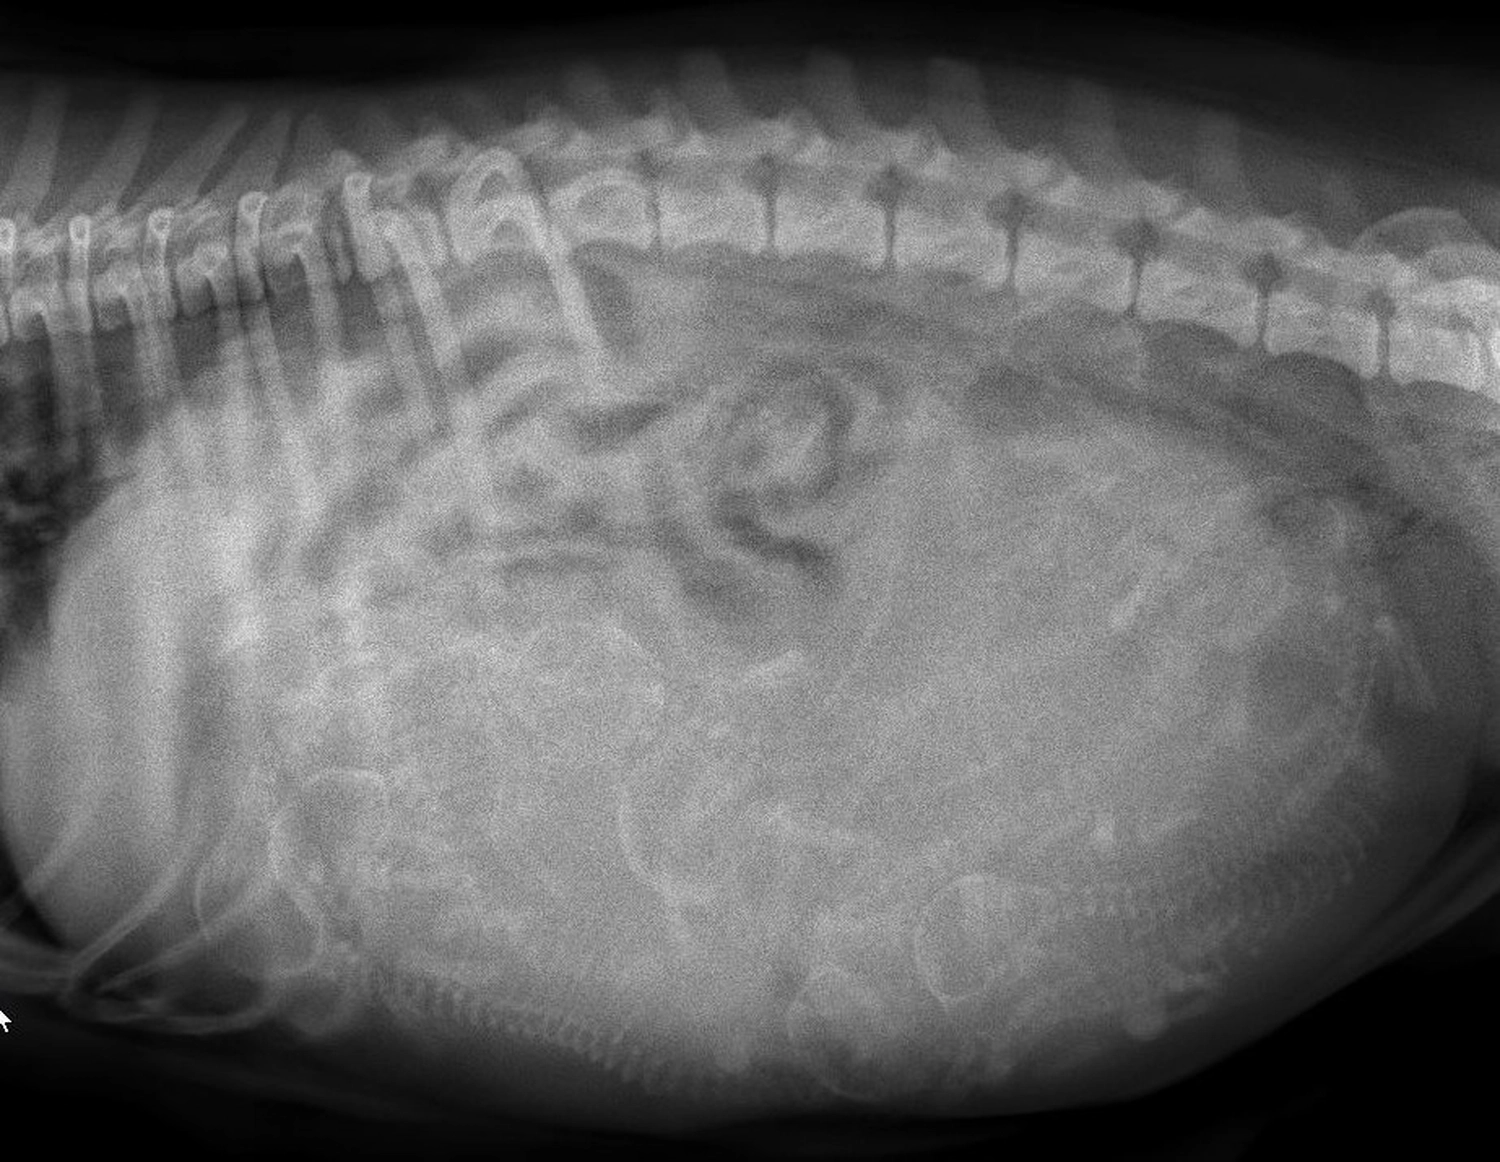

„Lilly war heute beim ‚Fotoshooting‘ der besonderen Art.

Na, erkennt ihr, wie viele kleine Wunder sich da verstecken?

Wir sind überglücklich über die positiven Neuigkeiten vomTierarzt. In wenigen Tagen ist es so weit – bleibt gespanntauf die ersten Baby-News!“

Die heutige Ultraschalluntersuchung bestätigte, dass Lilly trächtig ist.

Laut Tierarzt sind "6-8 Welpen" zu sehen!